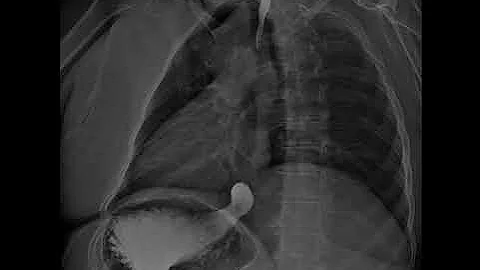

Dynamic X-ray Retrospective View Of The Esophagus In Motion | Konica Minolta Healthcare

Experience the incredible detail of Dynamic Digital Radiography (DDR) technology as we take a Retrospective look at the ...